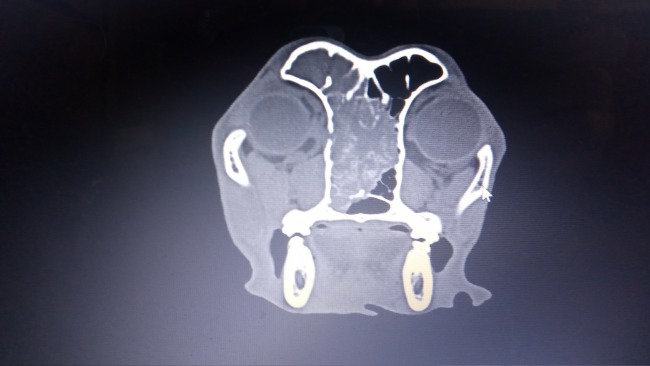

Ogi kichał od początku. Kichał strasznie. Z noska wyciekały mu gluty we wszystkich kolorach - od białych, żółtych, zielonych po brunatne. Aż zaczął kichać krwią. Próbowaliśmy go leczyć antybiotykami, sterydami, robiliśmy posiewy, był na zabiegu rinoskopii, który nic nie wykazał. Zdecydowaliśmy się na tomografię komputerową, która niestety pokazała nam ogromną zmianę. Nowotwór zajmuje prawie całą przestrzeń w nosie, przebija się do mózgu i gałek ocznych. Zniszczył też kość między oczami do tego stopnia, że pojawił się tam odstający guz.

W klinice pobrano wycinek guza, z pomiędzy oczu. Jednak biopsja dała niejednoznaczny wynik. Są tam komórki mięsaka - niemożliwego do wyleczenia, i chłoniaka - możliwego do wyleczenia.